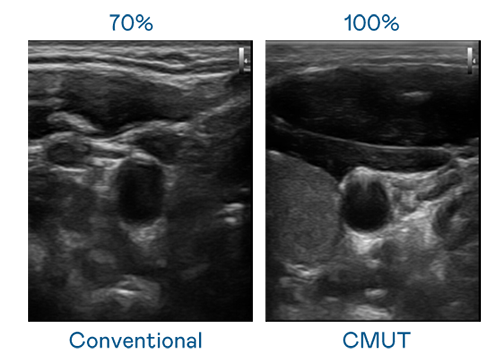

CMUT 技术是一种用电容式微机电元件来产生超音波讯号的技术。与传统 PZT 压电式技术相比,CMUT 频宽增加 30%,更宽频的超音波讯号让影像解析度大幅提升,是实现高影像品质医疗超音波扫描、促进精准医疗发展的关键技术。

超音波影像的解析度高低,首先取决于探头能发出的讯号频宽。极速3D CMUT 可提供高清晰的超音波讯号,提供高频宽、高灵敏度、影像纹理细节更高的超音波影像,协助医护人员缩短影像判读时间及利用精准的医疗影像进行诊断。